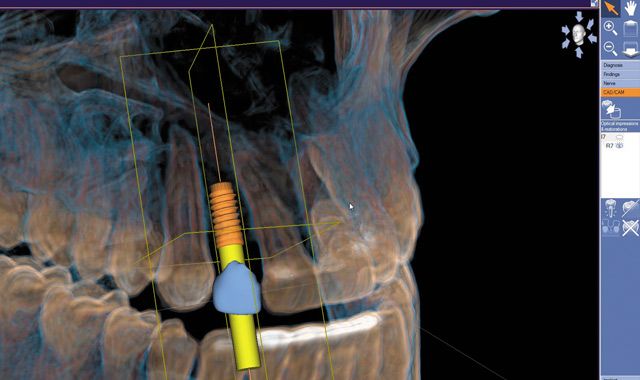

Fig. 11 The implant sleeve system was modified to the CEREC Guide 2 for guided surgery.

Fig. 12 A comprehensive implant plan was exported to the laboratory’s inLab SW 15 via a completely digital workflow.